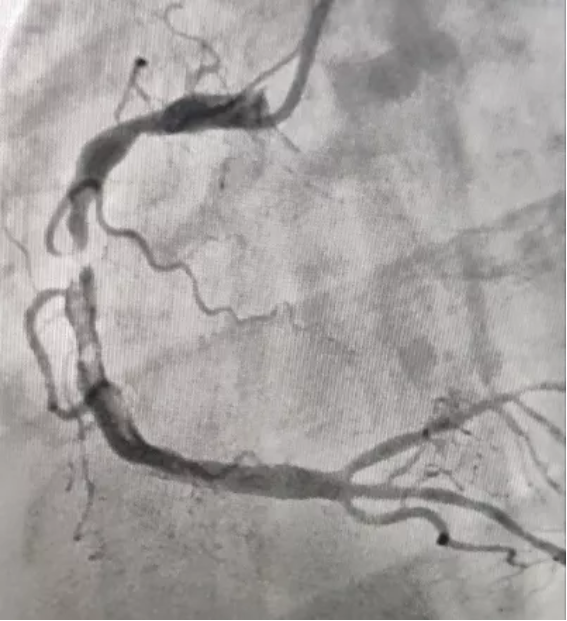

抽出的血栓

支架前